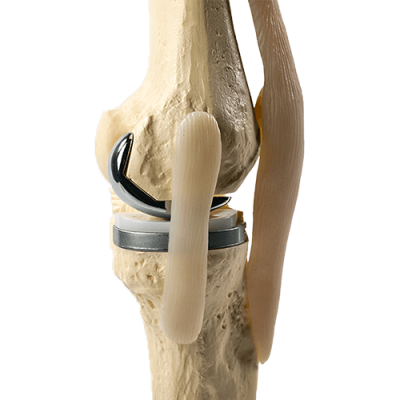

Фотографии и примеры протезирования коленного сустава